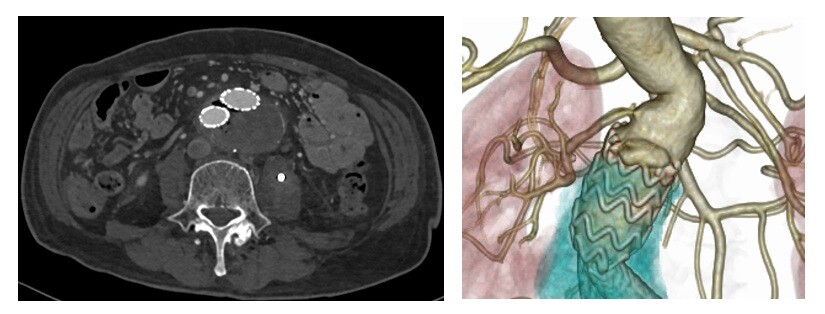

写真はステントグラフト術後5年でタイプⅠエンドリークが出現し、瘤が拡大したため人工血管置換術を行った症例です。ステントグラフトを部分切除して、拡大した動脈瘤を切し、人工血管に置換しました。

術前 術後 - 出血しやすい。出血したらとまりづらい。